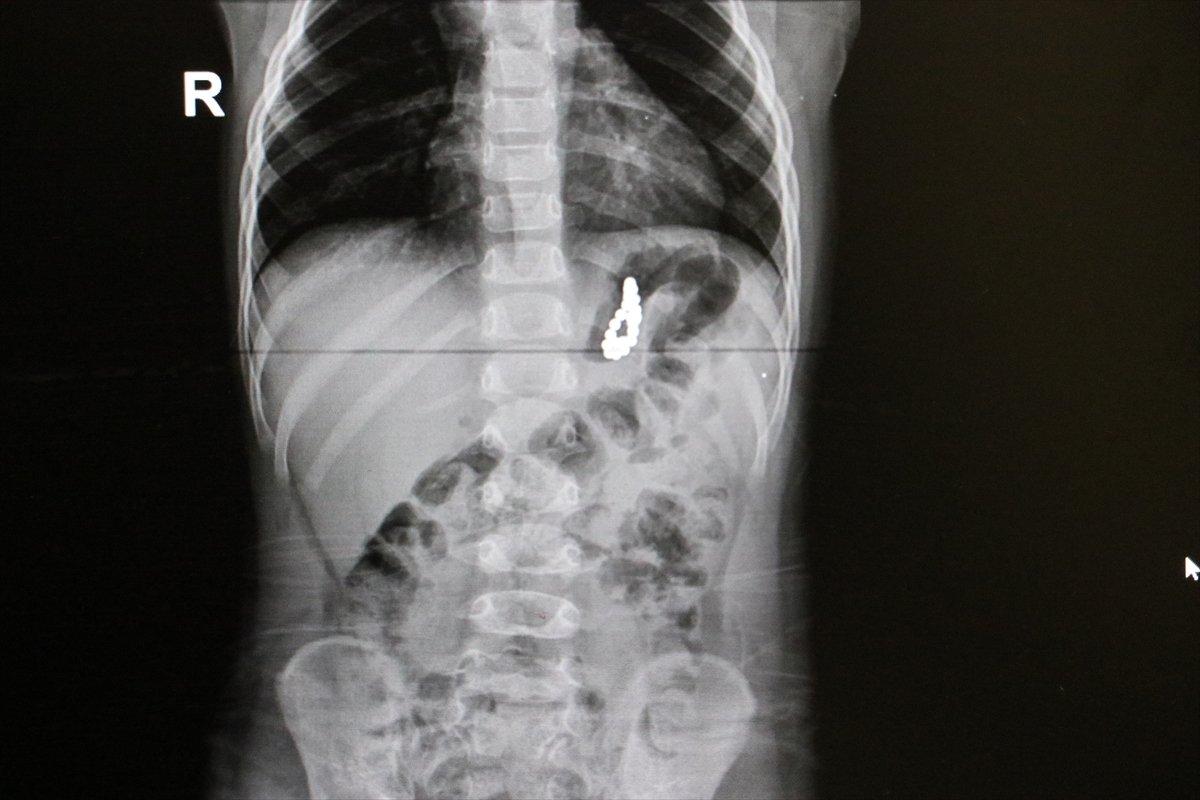

Akciğer enfeksiyonu şikayeti üzerine çekilen röntgende, çocuğun midesinde yabancı cisim bulunduğu tespit edildi.

Midedeki boncuk şeklindeki mıknatısların bir arada toplanması, röntgen ve endoskopi görüntüsüne de yansıdı.